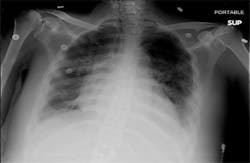

Posteroanterior chest radiograph shows bilateral pleural effusions with

bilateral atelectasis.

On examination, the patient was in mild distress with diffuse rhonchi in

bilateral lung fields. A chest radiograph demonstrated bilateral alveolar

and interstitial opacities, blunting of the costophrenic angles bilaterally,

and bilateral pleural effusions. Impression was bilateral pneumonia with

stable pulmonary edema and bilateral pleural effusion (see Image 1).